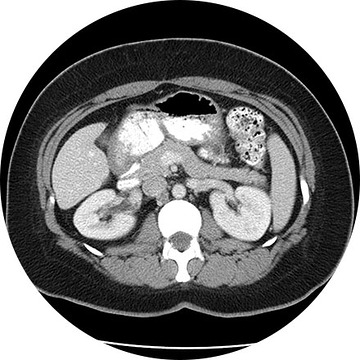

3.CT(전산화 단층촬영)

흉부 CT 촬영은 흉부 엑스레이보다 폐암을 발견할 수 있는 확률이 높고 이로 인해 폐암을 조기 발견하여 사망률은 낮출 수 있습니다. 저선량 CT는 방사선 조사량을 기존 CT에 비해 현저하게 줄이는 검사 방법으로 방사선에 노출되는 위험을 줄일 수 있습니다. 이 검사 방법은 해상도는 저선량이라서 기존 CT에 비하여 감소하지만 병변 유무를 관찰하는 데는 충분하며 간편한 검사입니다. X-ray에서 발견이 어려운 초기 폐암의 경우 흉부 CT 촬영을 통해 조기에 발견할 수 있습니다.